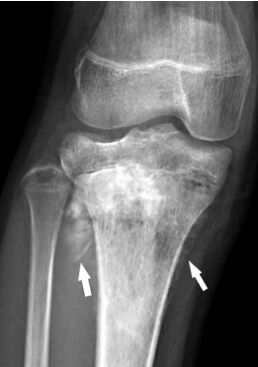

73.附圖是一位13歲女性脛骨骨肉瘤(osteosarcoma)的膝部X光影像,箭頭所指的影像表現是下列何者? (A)遊動體(loose body) (B)軟組織鈣化(soft tissue calcification) (C)骨膜反應(periosteal reaction) (D)骨折(fracture)